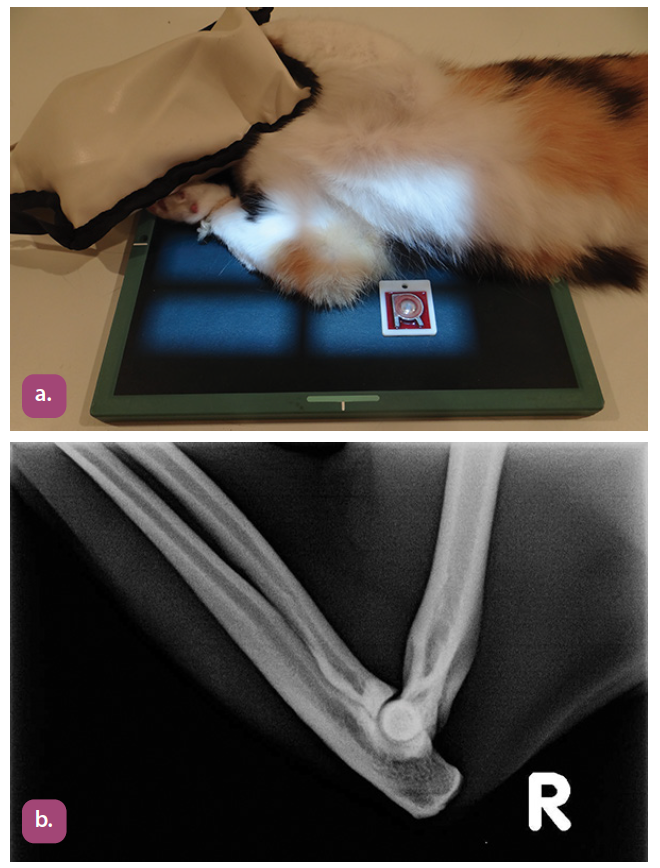

mediolateral projection of the elbow

flexed mediolateral projection of the elbow